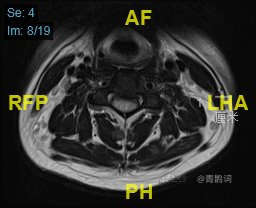

颈部磁共振平扫:

颈部磁共振平扫后增强: